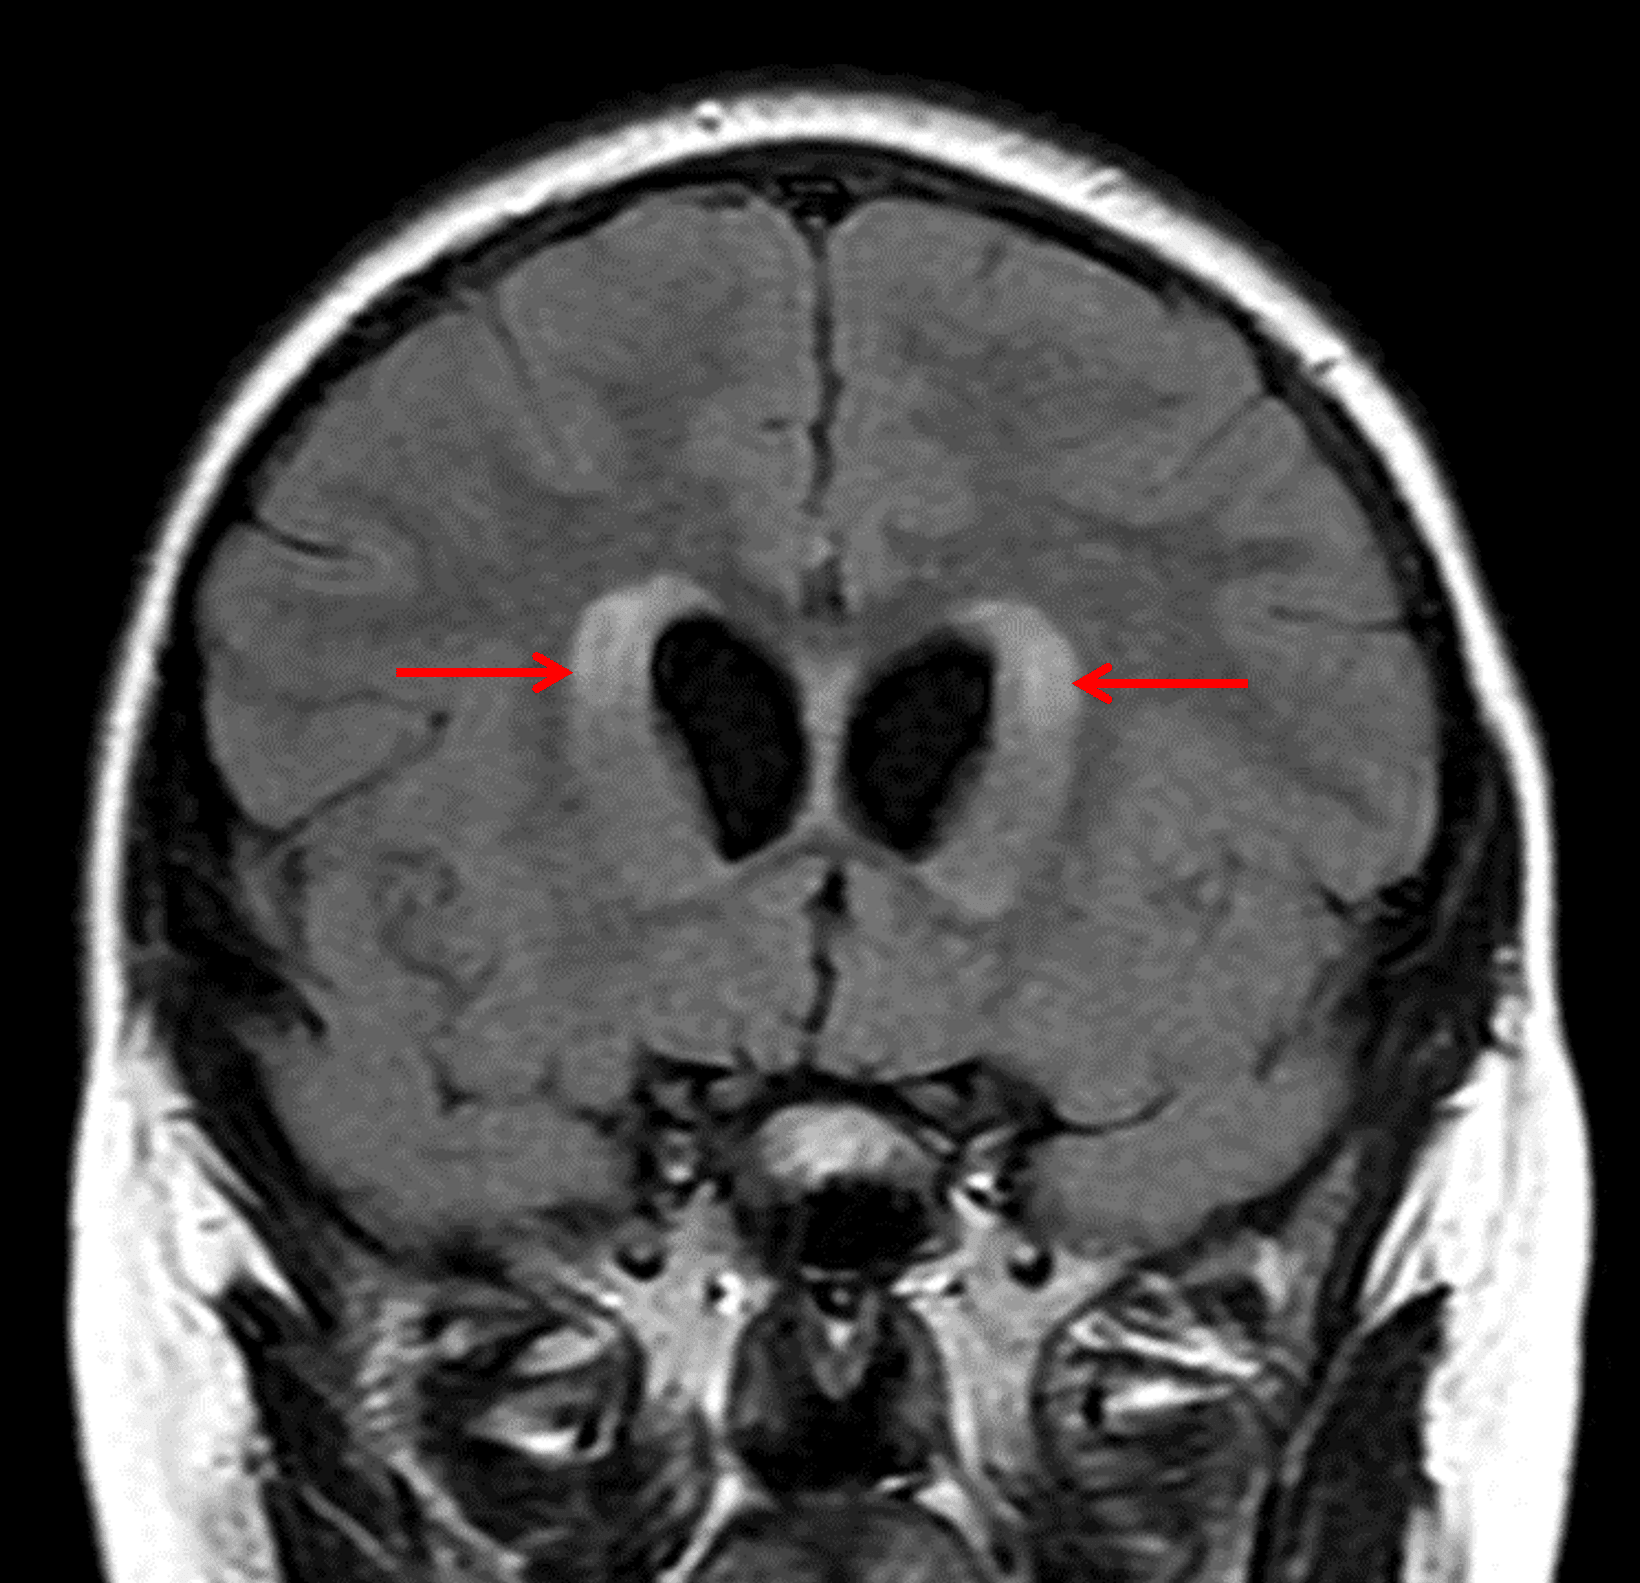

Associated obstructive hydrocephalus with subependymal edema (red arrows).